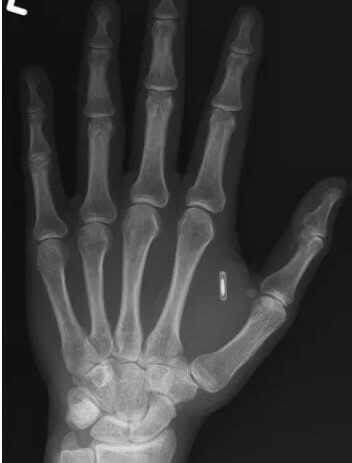

Со временем ссылка перестала работать, и он решил заменить её на новую. Но тут возникла проблема: он полностью забыл установленный пароль к чипу. Ван поделился рентгеновским снимком руки, где хорошо виден тот самый чип, и пошутил, что теперь он «потерял доступ к технологии, находящейся внутри собственного тела».